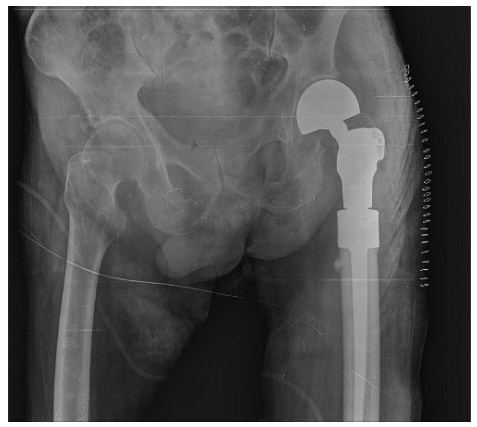

Post-surgery: The image shows the placement of a cemented tumor prosthesis on the upper end of the left femur.